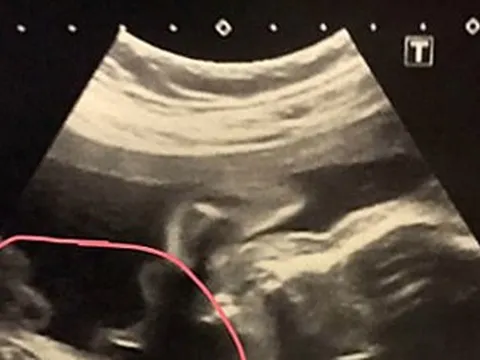

Kỳ tích tại Bệnh viện Hùng Vương: Cứu sống bé gái sinh non 23 tuần, nặng 640 gram

Bệnh viện Hùng Vương vừa tạo nên dấu mốc đặc biệt khi cứu sống và cho xuất viện một bé gái sinh cực non ở tuần thai thứ 23, nặng chỉ 640g. Sau 97 ngày điều trị căng thẳng trong phòng hồi sức sơ sinh, bé đã đạt 1.745g và được xuất viện.